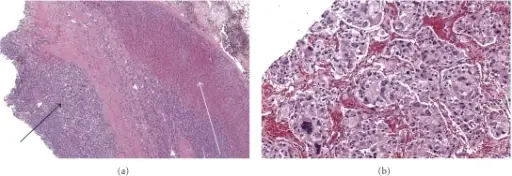

Adrenal Insufficiency

Adrenal insufficiency, commonly known as Addison’s disease, is a rare disorder that develops when the body doesn’t generate enough of specific hormones.

Waterhouse-Friderichsen syndrome, a group of symptoms caused when the adrenal glands fail to function normally that can cause acute insufficiency.

Features of Waterhouse-Friderichsen syndrome include:

- Hemorrhagic necrosis of the adrenal glands, which is typically brought on by disseminated intravascular coagulation (DIC) in young children who have Neisseria meningitidis infection

- Hypotension is made worse by cortisol deficiency, frequently resulting in death

Chronic adrenal insufficiency, or Addison disease as it is commonly known, is brought on by the gradual loss of the adrenal glands.

Common causes of Waterhouse-Friderichsen syndrome include:

- Autoimmune destruction which is the most common cause in the West

- Tuberculosis is also a common cause in the developing world

- Metastatic carcinoma such as cancers arising from lung